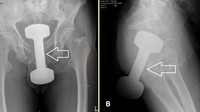

Pria 50 tahun datang ke IGD dengan dumbell 5 pon (2,2 kg) tersangkut di rektum. Setelah prosedur sedasi dan manuver khusus, barbel berhasil dikeluarkan dan pasien pulang dengan kondisi baik. (Foto: Cureus Journal)